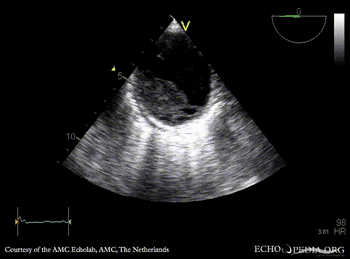

| TEE: dilated aorta | TEE: intramural hematoma of aorta |

| TEE: intramural hematoma of aorta | |